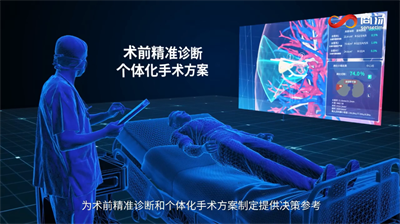

针对基于肺部CT的肺癌筛查,商汤科技SenseCare® Chest CT- Lung Nodule肺结节智能分析系统在全国多地医院落地应用,通过快速准确地识别微小结节,助力医生更高效更精准地进行潜在风险人群的筛查。

通过提取及重建胸部CT影像,系统可对胸部组织结构、脉管分布、病灶等进行三维智能交互式查看,方便医生进行更全面精准的术前评估。尤其是针对微小磨玻璃结节等术中较难定位的疑难病例,医生可以借助系统根据血管、气管的走形以及与病灶的相对位置进行小病灶的定位,帮助胸外科医生在术中也能精准找到结节。

例如一位患者在体检CT影像中发现肺结节病灶,其右下前基底亚段病灶附近有较为明显的血管穿行,且病灶周围密集的包围着肺动脉、肺静脉和气管的主要分支。如果直接进行肺叶切除,虽然较为稳妥,但是切除范围较大,会对患者的术后生活质量造成较为明显影响;可是如果进行S8b亚段精细切除术,由于病灶位置距离较大血管距离很近,术中操作不当极易引起明显出血。